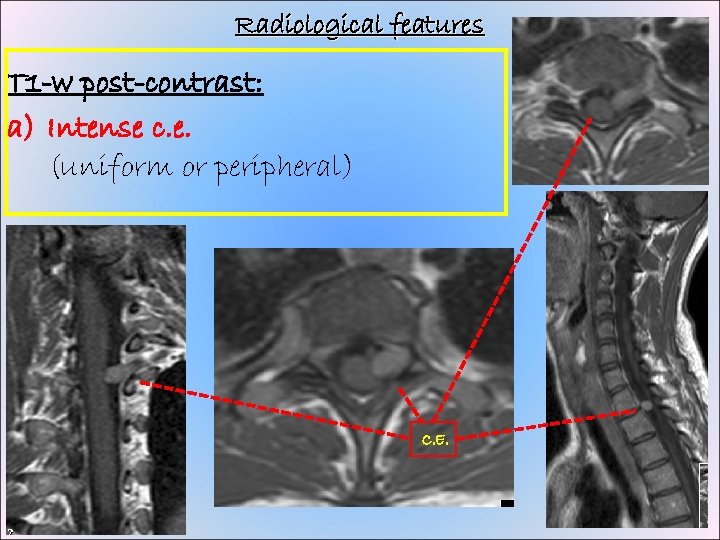

Radiological features T 1 -w post-contrast: a) Intense c. e. (uniform or peripheral) C. E.